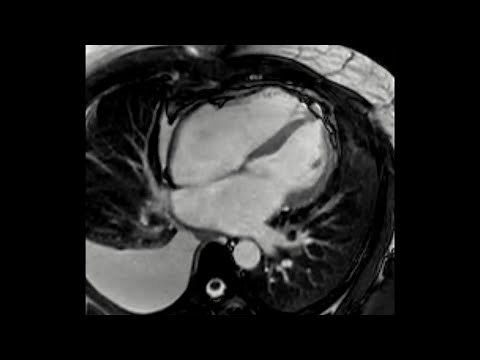

Cardiac Magnetic Resonance Finding in Constrictive Pericarditis

A patient presented with constrictive pericarditis. For pericardial characterization, cardiac magnetic resonance imaging (CMR) was performed. The real-time cine imaging sequence in the short-axis plane during free breathing is shown in the video, which demonstrates the displacement of the interventricular septum towards the left ventricle ...